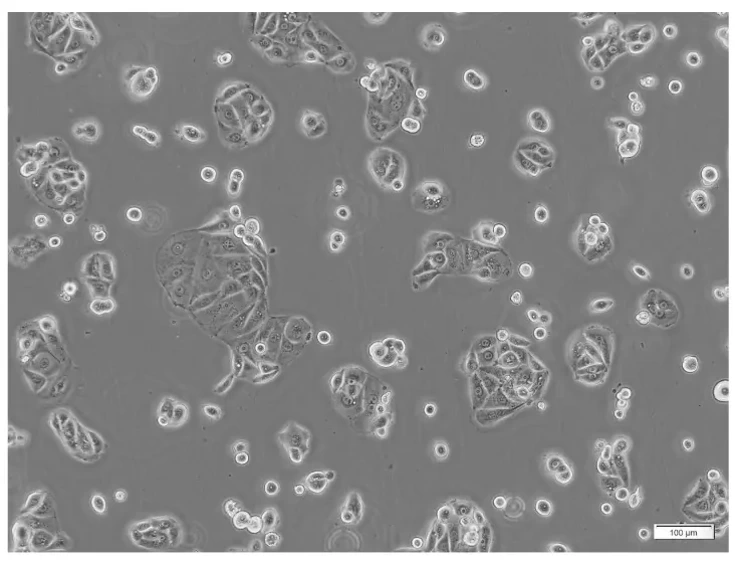

HT-1197 cells are epithelial-like adherent cells that form monolayers. Morphologically, these cells are polygonal to cobblestone, typical of bladder cancer cells. HT-1197 cells have been shown to proliferate rapidly and can be maintained with normal growth rates. Karyotyping and gene expression studies have shown HT-1197 cells to have chromosomal abnormalities and dysregulated expression of genes involved in important cellular pathways.